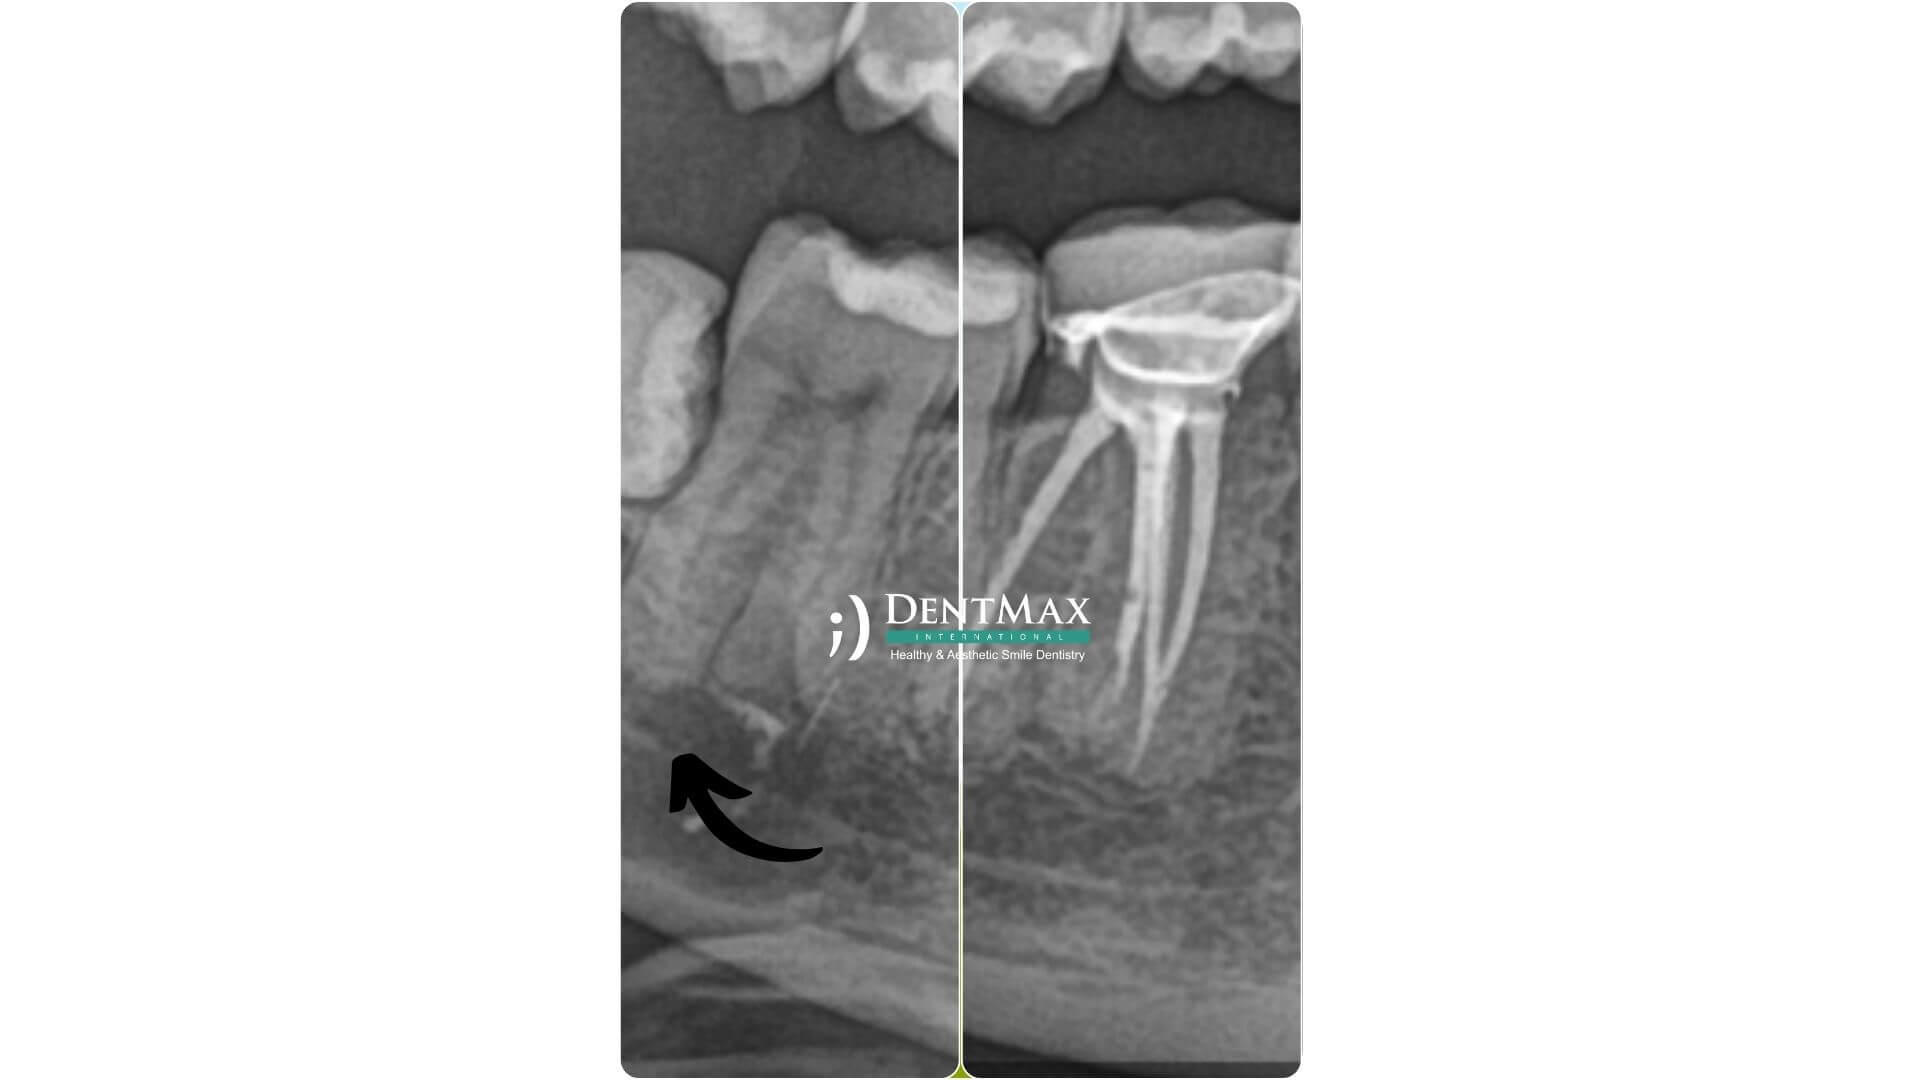

1. Muayene ve Röntgen: Diş hekimi, dişi muayene eder ve röntgen çekerek dişin durumunu değerlendirir.

6. Kanal Tedavisi Tekrarı:

• Daha önce yapılan kanal tedavisinin başarısız olması durumunda, tedavinin tekrarlanması gerekebilir. Bu durumda, eski dolgu materyali çıkarılır ve kök kanalı yeniden temizlenir ve doldurulur.